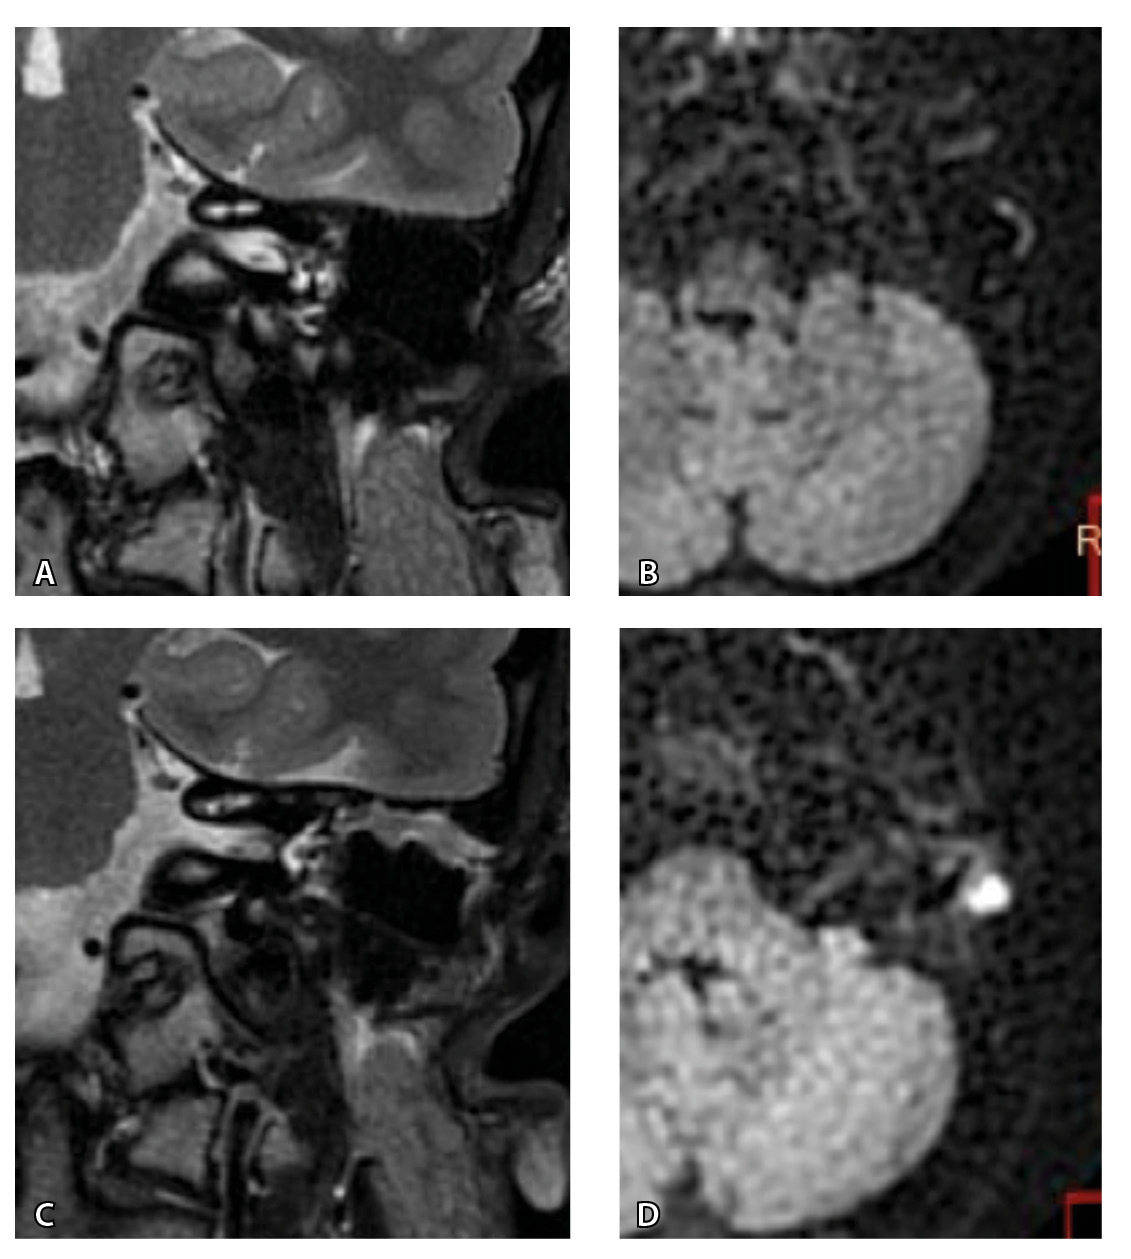

Рис. 3. Хронический правосторонний средний отит. По данным компьютерной томографии (А, Б) нет ремоделирования барабанной полости, деструкции и смещения косточек, скутум сохранен, данных за холестеатому нет. При магнитно-резонансной томографии (В, Г) у того же пациента выявлен очаг высокого магнитно-резонансного сигнала, который при слиянии локализовался в области пространства Пруссака. Заключение и интраоперационно – холестеатома пространства Пруссака